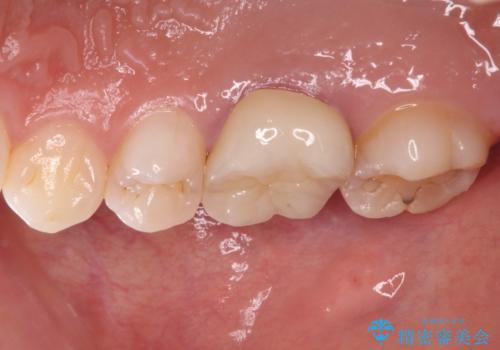

口腔内から、土台も含め銀歯がなくなったことでメタルフリーとなりました。